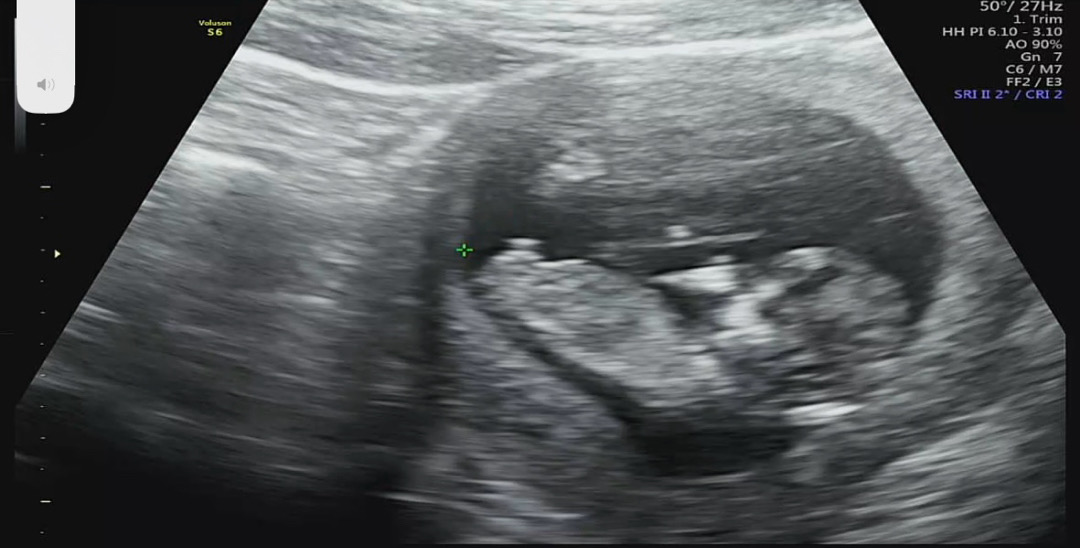

12주 각도법! 병원에서 성별 힌트 얻고왔긴한데 어때 보이시나용?.?

오늘 12주 2일차 1차 기형아 검사하러갔다가 선생님께서 성별 힌트주시더라구요.. ㅋㅋㅋㅋㅋ 이렇게 빨리 성별을 알수도 있나요? 각도법 고수맘님들은 어떻게 보이시나요오..??!!!

의사쌤도..정확한건 아니지만 🌶️래용ㅋㅋㅋ🤣

각도가 완전 하늘을보고있는..😆😆